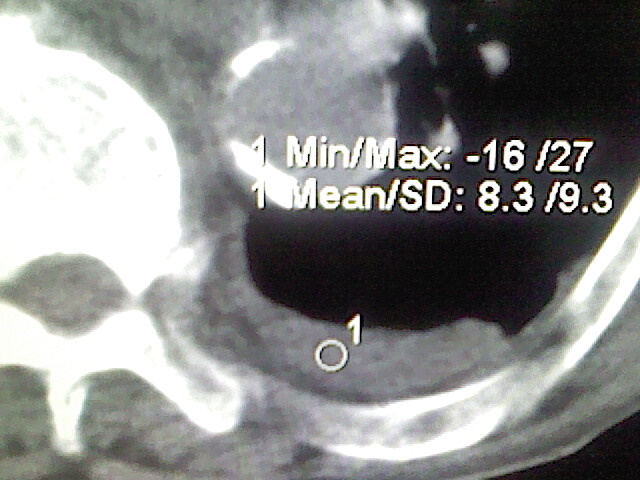

以下是引用zsl6918在2008-8-28 16:49:00的发言:[br]双肺炎性病灶,食管狭窄估计与心房增大压迫所致。

以下是引用xulianj在2008-8-28 20:36:00的发言:[br]慢支肺气肿伴感染,右上肺陈旧性结核;食道建议胃镜检查。

以下是引用wqs571018在2008-8-28 21:18:00的发言:[br]慢支继发感染,右上肺陈旧性结核;食道建议胃镜检查。